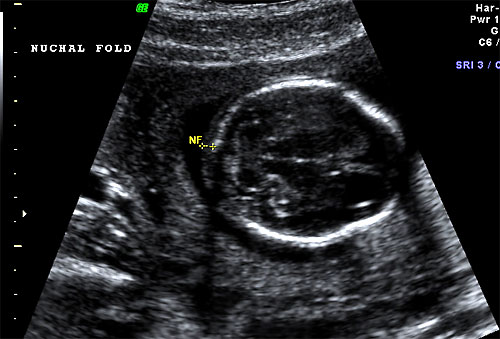

Normal 16 week nuchal fold |